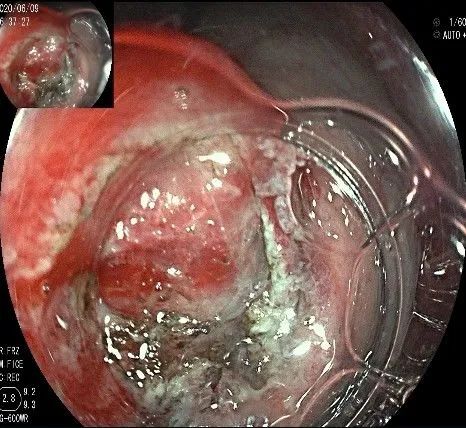

随着剥离的进行,瘤体与周围组织的关系越来越清晰。

此时瘤体基底部已暴露出来,起源于固有肌层。

这是最后的“根”部。

换用IT刀可以轻松剥离,又避免切入过深造成穿孔。

剥离接近完成,最后连接的薄层组织。